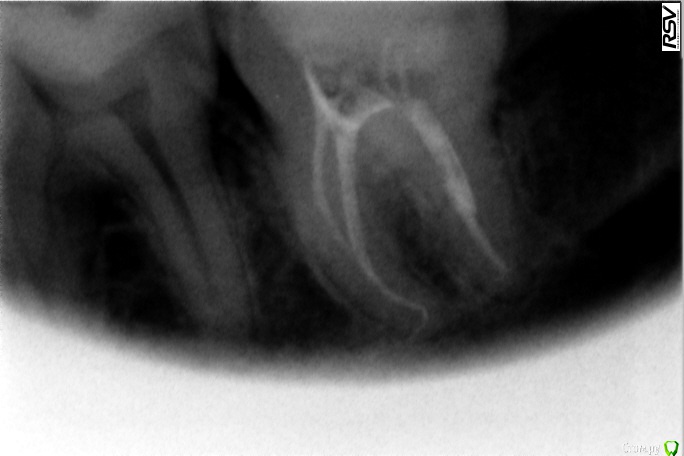

katrineigma Опубликовано 10 октября, 2015 Поделиться Опубликовано 10 октября, 2015 (изменено) Добрый день.Мне депульпировали зуб, дней через 5 после этого он начал просто невыносимо болеть, врач сказал, что зуб запломбирован хорошо, немного выведен пломбировочный материал за верхушку корня, но это не страшно, просто постпломбировочные боли. Дней 10 жила на обезболивающих, потом болеть все перестало. Сейчас прошло 4 месяца с того момента, зуб стал периодически ныть, сделала рентген в другой клинике - воспаление. Врач этой клиники говорит, что вряд ли такое воспаление может быть из-за выведенного за пределы корня материала, и вообще его не так много выведено, скорее всего, когда делали зуб, не нашли просто еще один канал и он остался пустым, от того и воспаление. Очень хотелось бы услышать мнения, в чем реальная причина воспаления всё-таки, и рекомендации, что теперь делать с зубом, можно ли его перелечить и нужно ли, или лучше не трогать? Прикладываю 2 снимка сразу после пломбировки каналов и 1 свежий, с воспалением.Заранее спасибо. Изменено 10 октября, 2015 пользователем katrineigma Ссылка на комментарий